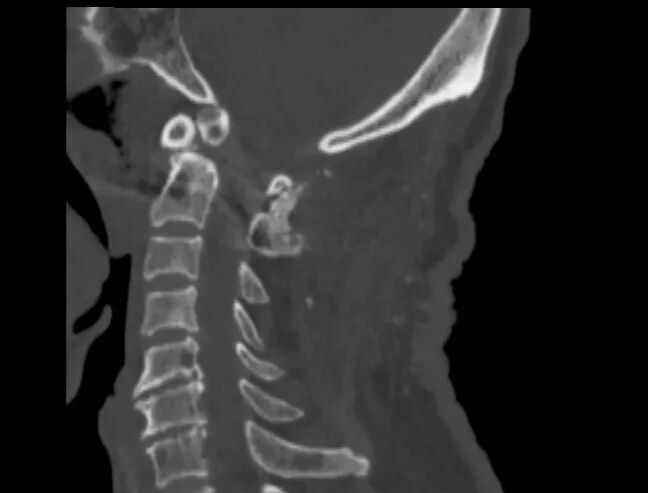

▲术后

手术全程顺利、创伤小、出血少,术后患者颈部疼痛明显缓解,肢体功能逐步改善,生命体征平稳,康复进展顺利。老人及家属连连致谢:“赶在春节前治好病,终于能过个安稳年了!

为最大限度保障患者安全与疗效,文昌院区骨科一区团队联合麻醉科、心血管内科、老年病科等多学科进行全面评估,反复优化手术方案,制定周密的应急预案。最终采用后路寰枢椎侧块钉棒系统内固定+植骨融合术:在影像导航辅助下,毫米级精准置钉,完美避开椎动脉与神经根;稳妥复位脱位关节,彻底解除脊髓压迫;采用坚强内固定+植骨融合,实现短期稳定、长期融合的理想效果。